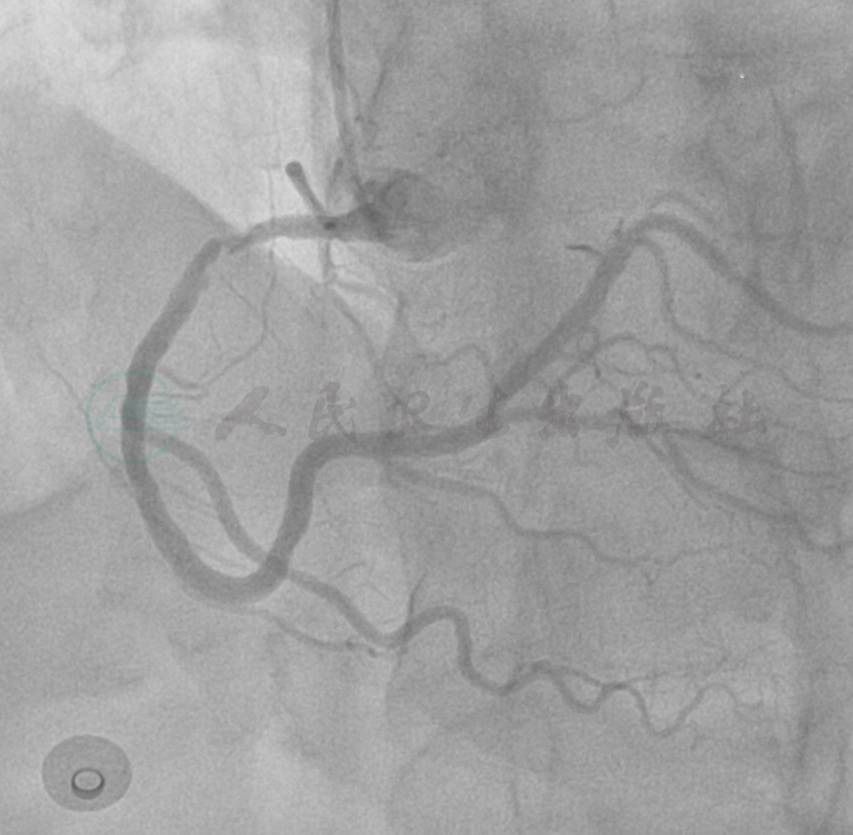

选用右桡动脉径路,6F血管鞘。造影发现:左主干可见斑块,前降支近段100%闭塞,侧支来源于右冠;右冠近段狭窄约90%(图1~图3)。

图1 左主干可见斑块,前降支近段100%闭塞

图2 左冠造影2